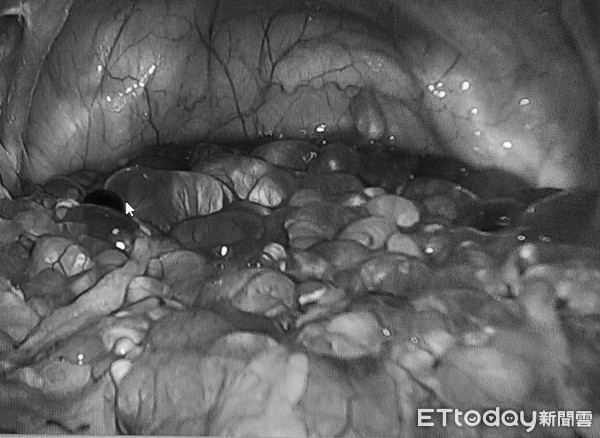

Hàng trăm u nang trong khoang chậu của phụ nữ.

Sau khi hội chẩn, bác sĩ Lý nhận định đây là một khối u lành tính, những u nang trong cơ thể bao trùm bất thường. Có quá nhiều u nang dính chùm với nhau như những viên bột trân châu, bám đầy quanh sàn chậu.